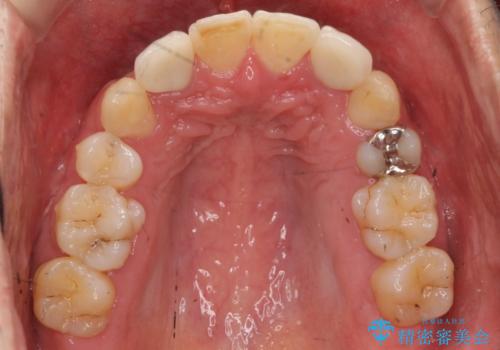

八重歯の矯正+歯のないところにインプラント

下の歯がないところに、奥歯が倒れこんでいたため、矯正治療で倒れこんだ歯を起こして、インプラントを植立しました。

- 197万円 (矯正治療95万円、インプラント治療72万円(下顎両側6)、その他補綴治療30万円(上顎両側2))費用は治療当時の料金となります

上顎の小臼歯2本、下顎の親知らずを抜歯しています。

八重歯の移動のため、矯正用ミニスクリューを使用しています。